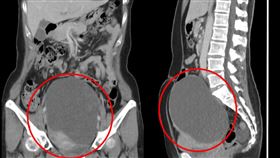

49歲婦肚子變大 竟是16公分腫瘤塞滿卵巢

今年49歲的家芸於去年中罹患卵巢癌,但她不僅沒有感到...

2024/03/12 08:39